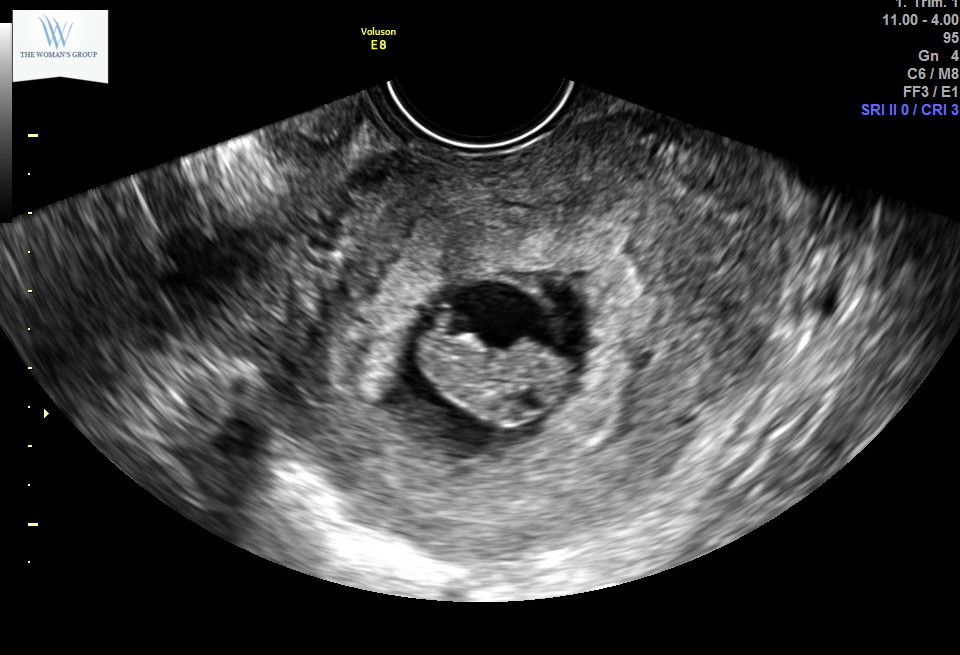

Second ultrasound! I’m 9 weeks today and baby is measuring 8wks 4 days. Within the margin so they’re keeping my 7/11 due date. Strong heartbeat at 178!